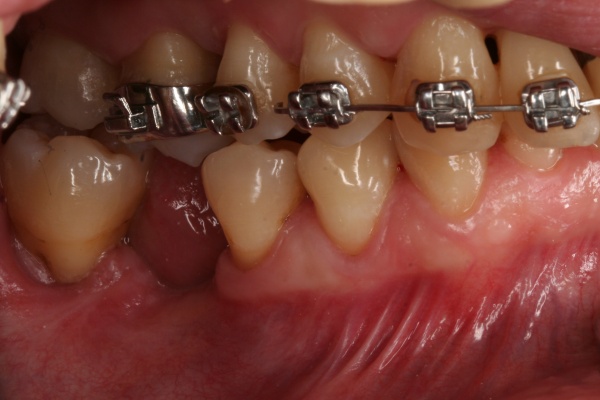

In der prächirurgischen Phase muss ein besonderes Augenmerk auf die prognostische Einschätzung der parodontalen und dentalen Situation gelegt werden. Dabei ist insbesondere auf die allgemeinmedizinische und spezielle dentale Anamnese zu achten. Bornstein et al. (2009) untersuchten den Einfluss von Allgemeinerkrankungen auf die Periimplantitis. Unter anderem Safi et al. (2009) wiesen auf die Bedeutung einer Parodontitishistorie hin. Aber auch die Lebensgewohnheiten des Patienten haben einen entscheidenden Einfluss (Tabakkonsum, ungenügende Mundhygiene, fehlende Nachsorge [Heitz – Mayfield & Huynh – Ba 2009]) (Abb. 3).